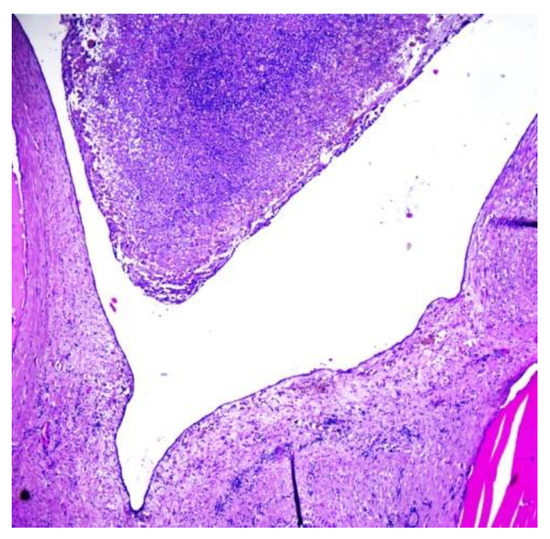

The histopathological examination of the multilocular cystic mass was consistent with benign SO, as its walls were composed of mature thyroid tissue without architectural or cytological atypia, with variable-sized follicles containing eosinophilic colloid (Figure 6). The stroma between the follicles was fibrous with focal extracellular cholesterol deposits. The largest cyst was lined withflat epithelium, with some thyroid follicles in the fibrous walls. The content of some small cysts was represented by purulent exudate (Figure 7). No other epithelia were detected.

Figure 7. Histopathological aspect of a cyst lined withflat epithelium, containing purulent exudate (H&E stain, magnification: 40×).